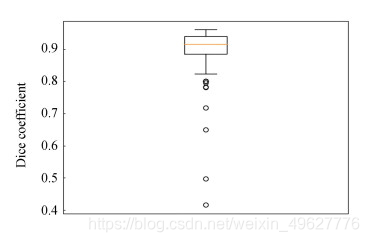

图 8为测试集57例样本的评价指标Dice分布图,对比图 8(a)和(b)可知,单模态网络中有4例样本远离集群点,而多模态仅有2例样本远离集群点.

图 8 脑肿瘤测试集Dice分布